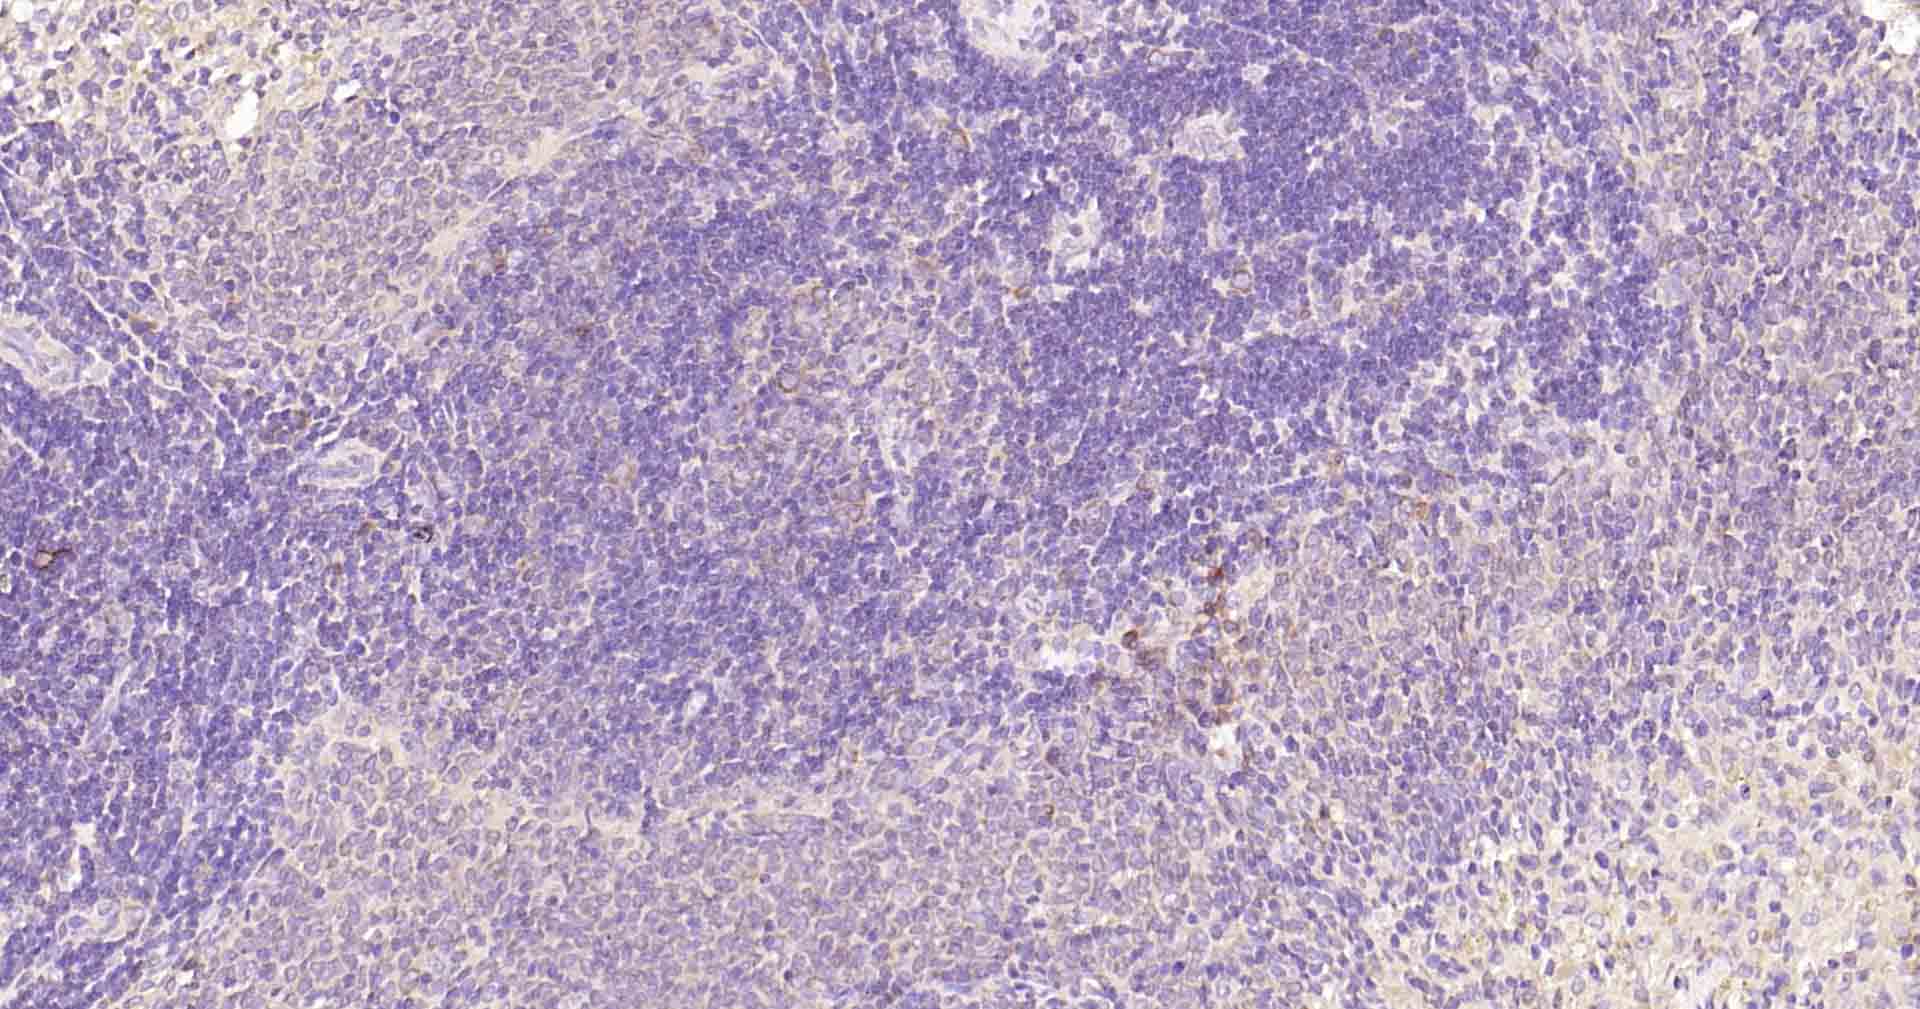

Paraformaldehyde-fixed, paraffin embedded Rat Spleen; Antigen retrieval by boiling in sodium citrate buffer (pH6.0) for 15 min; Antibody incubation with Beclin 1 Monoclonal Antibody, Unconjugated(bsm-41365R) at 1:50 overnight at 4°C, followed by conjugation to the SP Kit (Rabbit, SP-0023) and DAB (C-0010) staining.